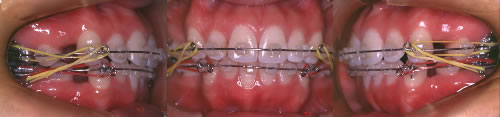

写真4 ワイヤーを装着して歯並びを矯正している、治療中の口腔内写真。

写真5 前突が徐々に矯正され定着し始めているところ。